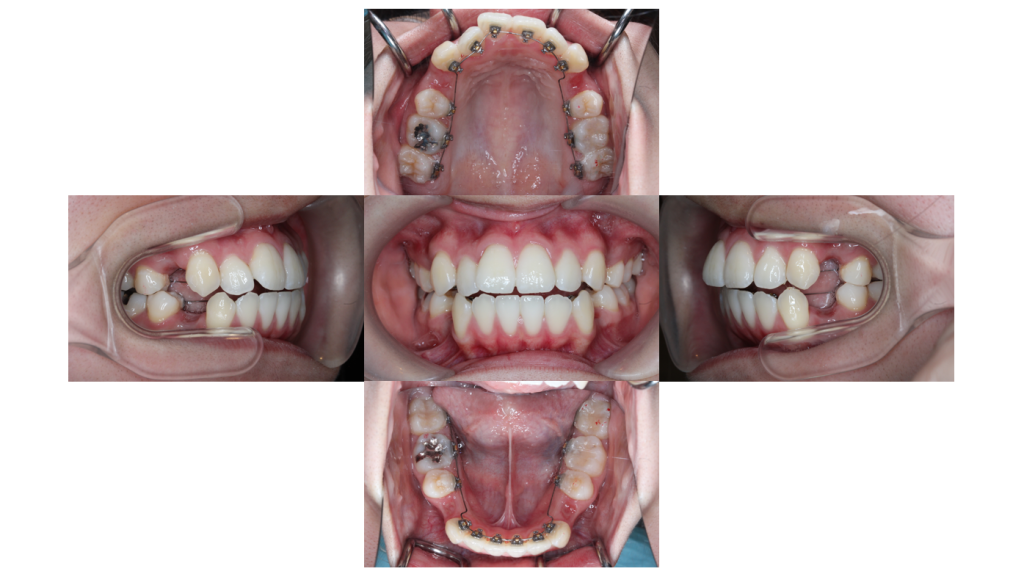

上下装置装着

叢生・裏側矯正の症例上下装置装着後の口腔内です。